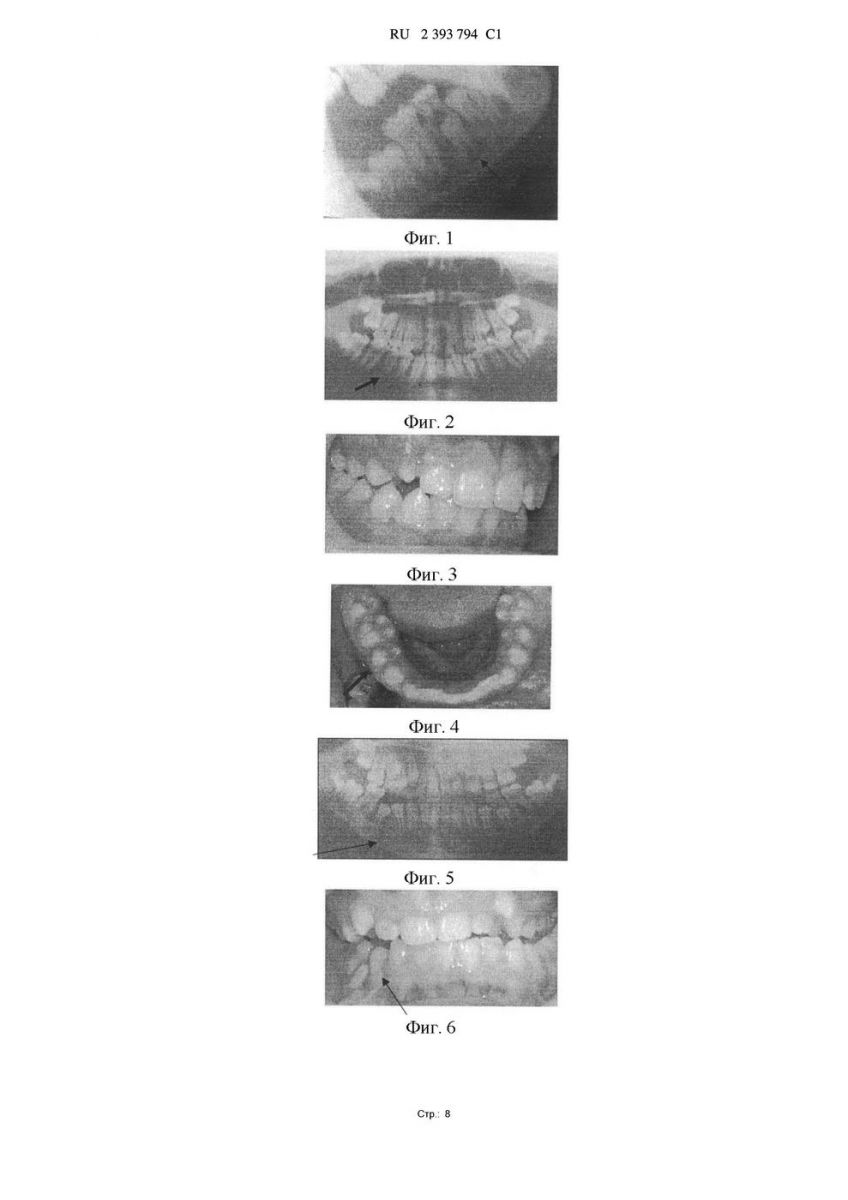

При контрольной панорамной рентгенографии челюстей через 1 сутки после хирургического вмешательства материал рентгенонегативен. Зачаток 45 зуба находился в заданном положении. На рентгенограмме через 1 месяц после операции область дефекта заполнена остеогенной тканью с четко контурированными костными балками, 45 зуб полностью сформирован и находится в правильном положении в зубном ряду. На панорамной рентгенограмме челюстей через 2 месяца границ кистозной полости не наблюдается. Костная ткань нижней челюсти имеет однородную структуру. 45 зуб прорезался в правильном положении (фиг.2, 3, 4).

Пример 2. Пациент М., 11 лет, поступил в отделение детской стоматологии с диагнозом - Зубосодержащая киста нижней челюсти справа. Жалобы на безболезненное «выбухание» в полости рта справа. Из анамнеза заболевания: 85, 84 зубы не лечили (фиг.5). Проведена операция под эндотрахеальным наркозом, цистэктомия с остеопластикой коллаген-апатитового композита «ЛитАр». Послеоперационный период осложнился нагноением раны. Ежедневно проводили промывания костной раны растворами антисептиков. Зуб 4.4 прорезался через 1 год в зубную дугу в правильное положение (фиг.6), зуб 4.5 прорезался с нарушением его —Úð.: 5 5 10 15 20 25 30 35 40 45 50 RU 2 393 794 C1 положения в зубном ряду, выражена инфраокклюзия зуба (фиг.7). Через 5 месяцев на панорамной рентгенограмме костная ткань в области дефекта восстановилась не полностью. Пример 3. Пациент С., 12 лет, после операции цистэктомия с остеопластикой коллаген-апатитовым композитом «ЛитАр» через 1,5 года. Зуб 4.5 во время операции был удален, зуб 4.4 находится в толще костной ткани, не прорезался (фиг.8, 9). Пример 4. Пациент Ф., 11 лет после операции цистэктомии с остеопластикой коллаген-апатитого композита «ЛитАр» через 3 года 2.3 зуб не прорезался, выражена его ретенция (фиг.10, 11). В результате проведенных операций у 32 пациентов цистэктомия с остеопластикой лиофилизированной деминерализованной губчатой аллокостью ранних и поздних послеоперационных осложнений не выявлено.